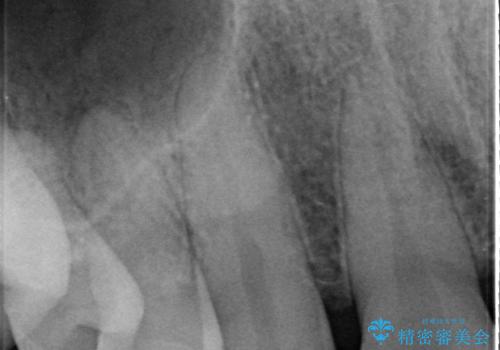

- 前歯部のすきっぱと歯並びが気になるので診て欲しいといらっしゃった方の症例です。

全顎矯正は御希望されなかったため、上顎前歯部のみの部分矯正とオールセラミッククラウンによる補綴を行いました。